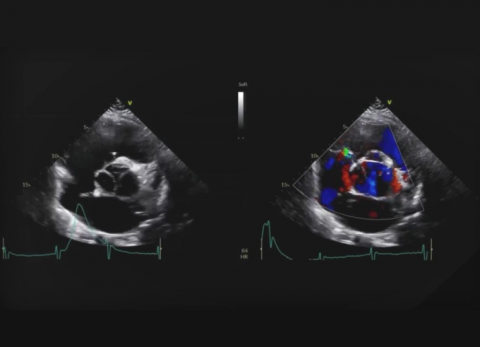

Wideo Echokardiografia. Przypadek 23

prof. dr hab. n. med. Olga TrojnarskaPacjentka z zespołem Marfana